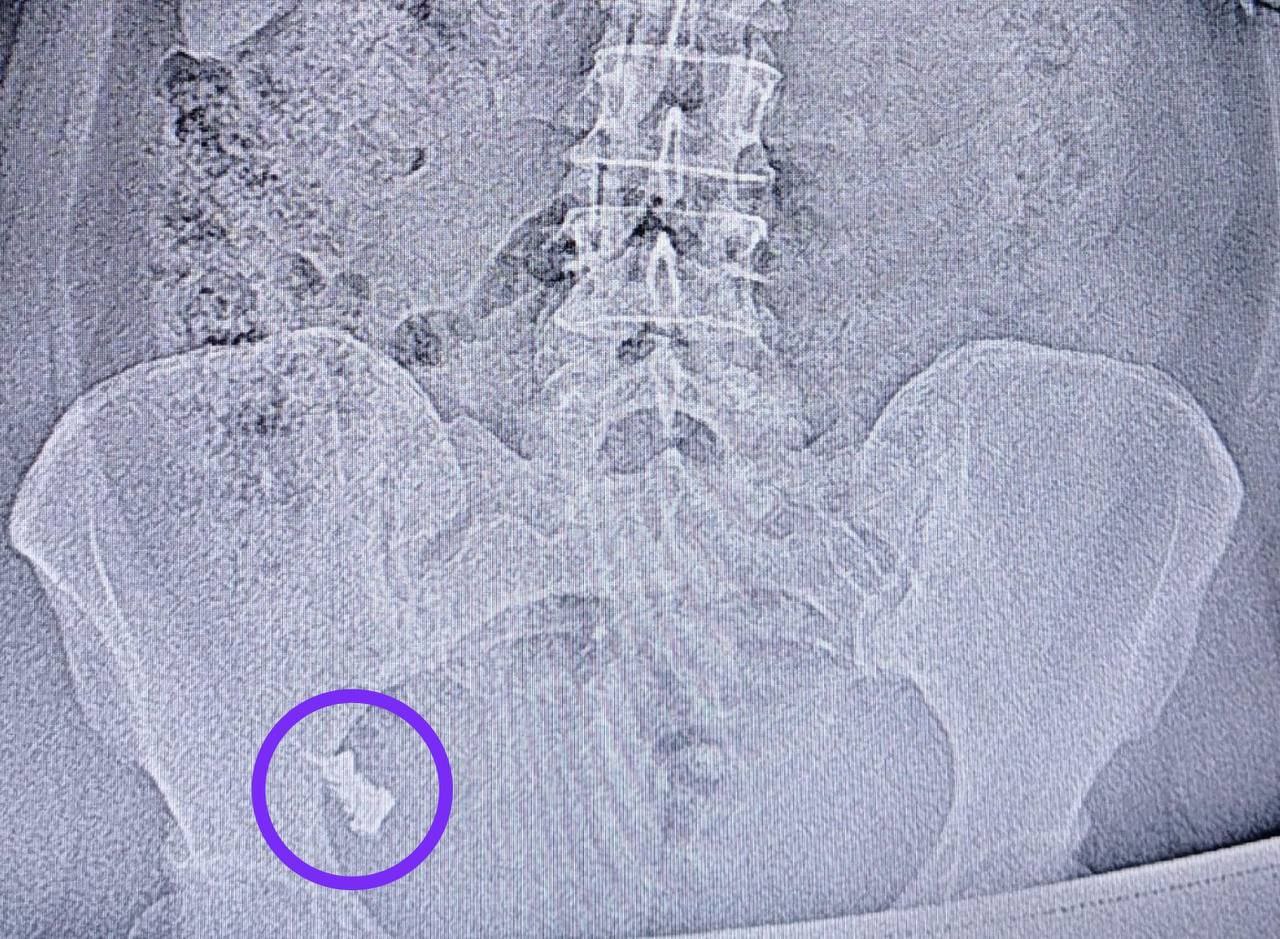

Что только оттуда не извлекали, в этот раз — протез. 50-летняя дама случайно его проглотила. Но панику решила не поднимать и обойтись без врачей, мол, сам выйдет. Но протез застрял на полпути.

Спустя неделю женщину срочно увезли в хирургическое отделение №1 и провели колонскопию. Зубы извлекали с анестезией, поэтому никаких душевных травм у пациентки не осталось. Но такие фокусы с исчезновением повторять не стоит.